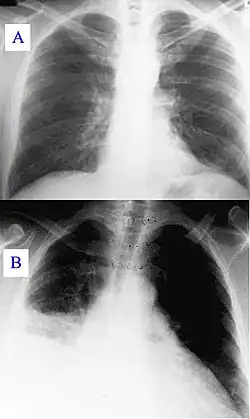

New or progressive infiltrate on the chest X-ray with one of the following:[3]

In hospitalised patients who develop respiratory symptoms and fever, one should consider the diagnosis. The likelihood increases when upon investigation symptoms are found of respiratory insufficiency, purulent secretions, newly developed infiltrate on the chest X-Ray, and increasing leucocyte count. If pneumonia is suspected material from sputum or tracheal aspirates are sent to the microbiology department for cultures. In case of pleural effusion, thoracentesis is performed for examination of pleural fluid. In suspected ventilator-associated pneumonia it has been suggested that bronchoscopy or bronchoalveolar lavage is necessary because of the risks of incorrect clinical diagnoses.[1][3]